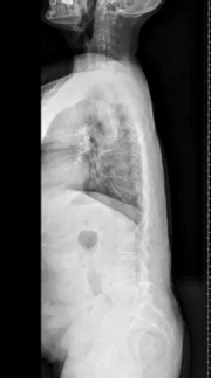

▲ 女,3岁4个月,先天性脊柱侧弯半椎体畸形

▲ 女,7岁,先天性脊柱侧弯半椎体畸形